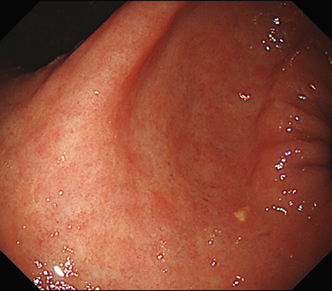

EVIS LUCERA ELITE × GIF1200N 症例画像

遠景部分において明るい視野が確保できる(血管の例)